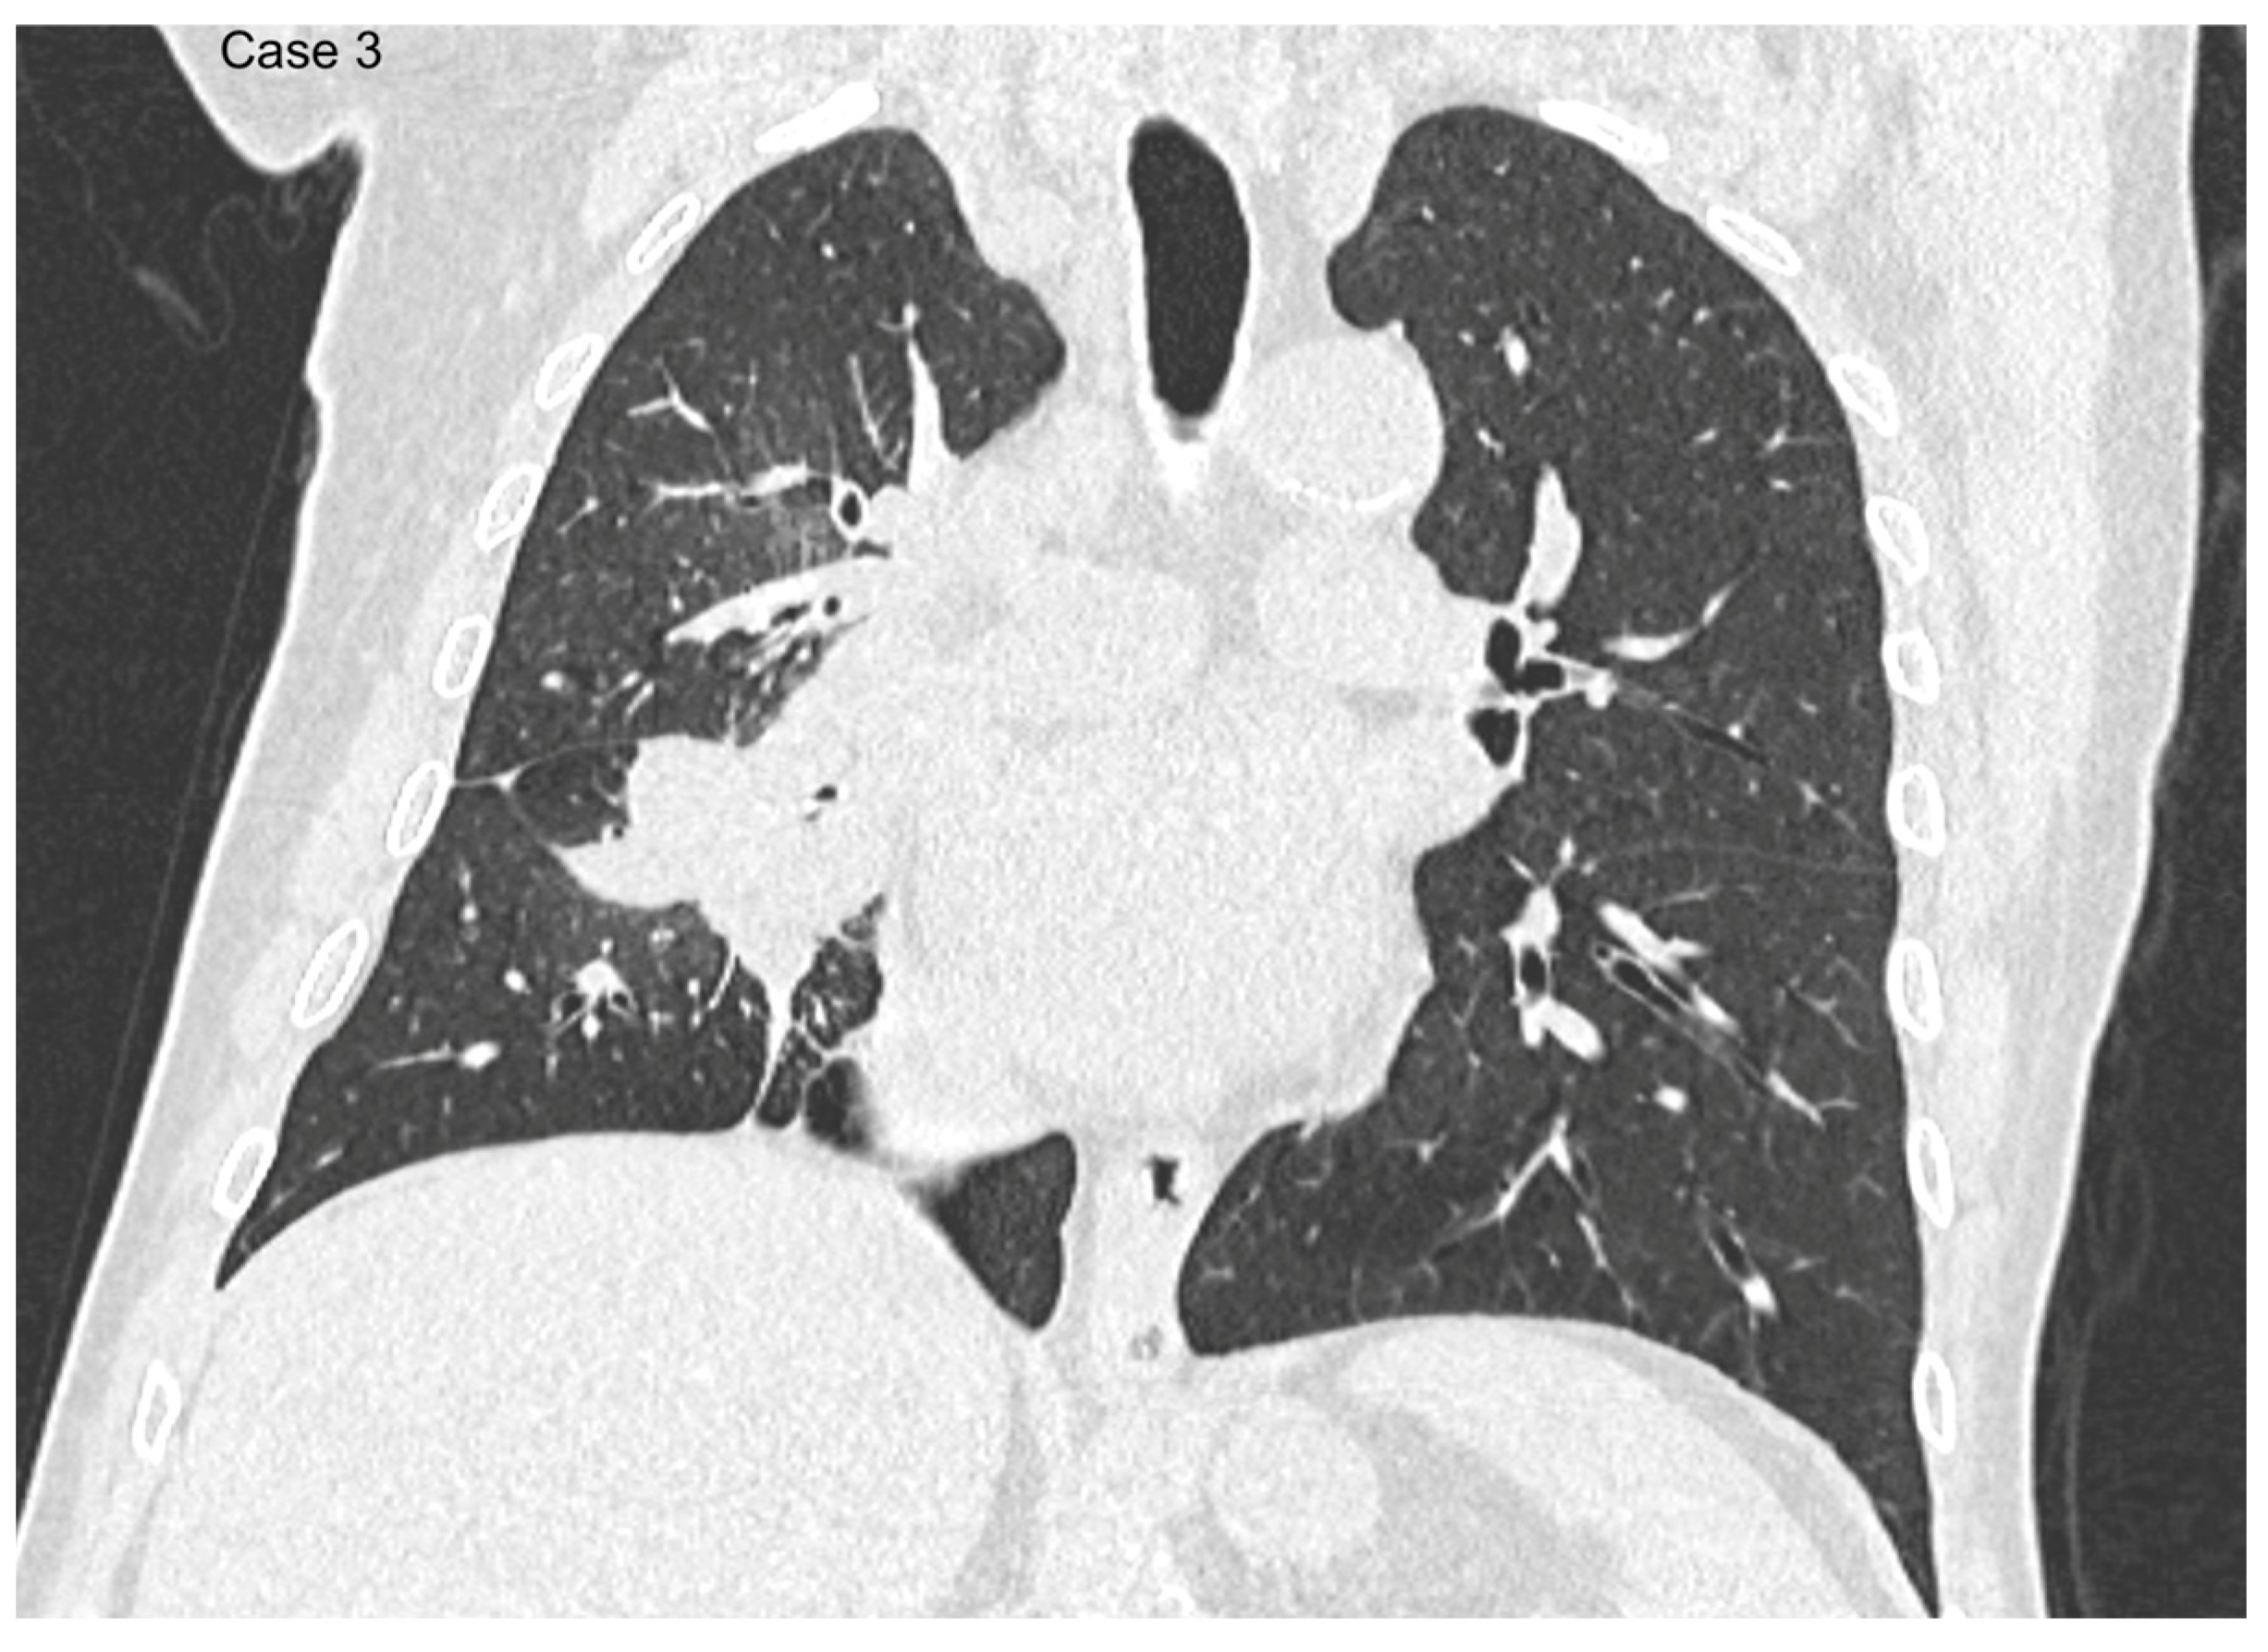

- Argentieri, G.; Valsecchi, C.; Petrella, F.; Jungblut, L.; Frauenfelder, T.; Del Grande, F.; Rizzo, S. Implementation of the 9th TNM for Lung Cancer: Practical Insights for Radiologists. Eur. Radiol. 2025, 35, 4395–4402. [Google Scholar] [CrossRef] [PubMed]

- Erasmus, L.T.; Strange, C.D.; Ahuja, J.; Agrawal, R.; Shroff, G.S.; Marom, E.M.; Truong, M.T. Imaging of Lung Cancer Staging: TNM 9 Updates. Semin. Ultrasound CT MRI 2024, 45, 410–419. [Google Scholar] [CrossRef]